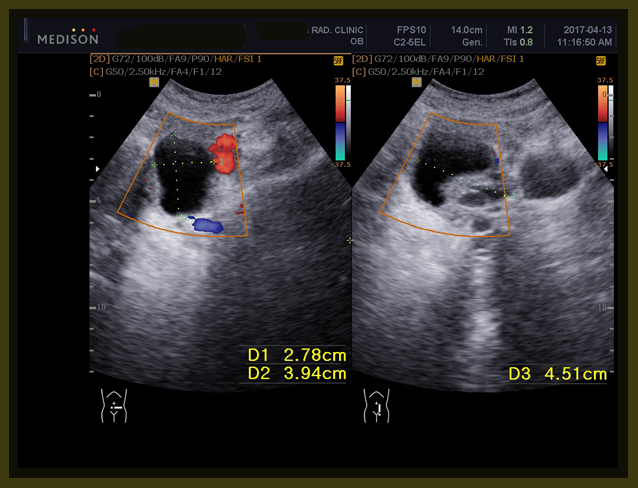

1-1

환자는 1년 전에 난소의 양성종양으로 수술을 받았던 경험이 있고, 이번에도 유방수술 이후에 초음파를 보니 83mm x 61 mm x 58 mm의 약 8cm x6cm 정도의 격벽으로 분리된 cystic mass 즉 액상의 종양이 보였고, 또한 13mm, 15 mm의  mass도 발견되었다(2017년 1월 26일 검사).

내원 후에 본원 의뢰하여서 초음파 검사를 하였는데 초음파상의 결과는 이전 병원과 약간의 차이가 있지만 역시 8cm가 넘는 종양이 발견되었다.

1. 6.8cm x 5.9cm x 8.1 cm 크기의 여러 개로 갈라진 격벽을 가지고 있는 액상의 부위가 왼쪽 자궁주위 조직에 보이는데 양성의 혹으로 보인다.

1. 6.8cm x 5.9cm x 8.1 cm 크기의 여러 개로 갈라진 격벽을 가지고 있는 액상의 부위가 왼쪽 자궁주위 조직에 보이는데 양성의 혹으로 보인다 (volume 171 CC).

2주간의 한양방 결합요법의 결과 3항에서 보듯이 약 7mm 정도의 전에 잔류 종양으로 보이던 부분이 약간 줄어들었고, 자궁주위에 있던 난소의 종양은 6.8×5.9x 8.1cm의 크기가 5.5×4.7×6.7cm 로 체적대비해서 171 cc가 91 cc로 100%의 종양이 53%로 절반 가량이 줄어들었고, 자궁내벽의 비후는 여전히 보이고, 3cm 크기의 근종으로 보이는 종양은 차이가 없었다.

1-9

1. A multiseptated cystic lesion in the left parametrium, cystic ovarian tumor, muchmore regressed(5.5×4.7×6.7cm/91ml ->2.8×3.9×4.5/25ml)

171 ml                                               91 ml                                           25ml